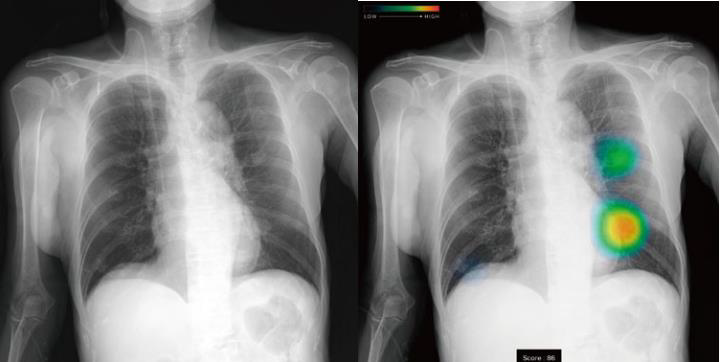

上記画像のように、病変が疑わしい箇所にはヒートマップが表示されます。

AIの確信度に応じて色合いが変わり、病変がある確率が高いほど赤い表示がされるため、視覚的にも非常にわかりやすくなっています。